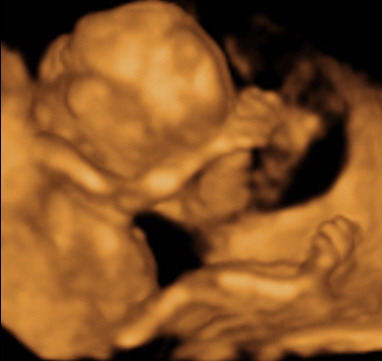

Ha esetleg nem látnátok: a lábai az égnek állnak, és közte a fütykös kb. akkora, mint a nyíl. (mármint golyszli és rajta a fütykös :wink: :lol: )

KépKép